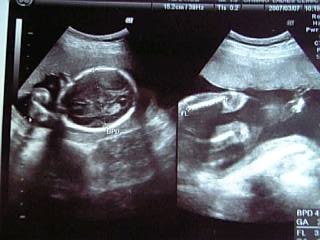

21weeks0days

ほんとは金曜日が病院の予定だったんすよ。

でも、どーしても性別が気になっちゃって行って来ちゃいましたw。

ジャ、ジャ~ン???

全く解りません・・・・

診察台にあがるまで

「先生におマタをどど~んと見せるのよ~」

っと何度も言い過ぎたせいか、なんとおマタ部分を手で隠してたそうなw

(正確にはおマタ近くに手があった&体勢のせい。)

起きてたみたいだったから

「ホレ、先生に見せんしゃいっ、ホレホレっ」

とお腹をスリスリしながらお願いしてみたけどムリw

「次回のお楽しみだな~こりゃ」

と必死に見てくれてた先生も諦めてしまった。

あ。先生からは何も言われなかったので

ベビの成長は順調・・と思う・・

なんかブツブツ言いながら イロイロ見てくれてたし。

体重が先月よりも1.4kg増えてて

「妊娠前からあまり増えてはいないけど、これからは食べすぎ注意だよ。」

と言われた^^;(妊娠前+3kg)

とまあ、そんなこんなで次回の検診は4週間後。

今度はベビが順調かどうかちゃんと聞いてみようww。

くぅーっ!待ちどおしいぞっ